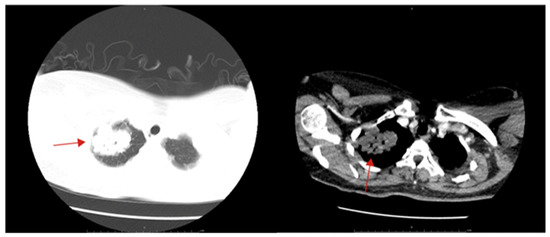

2. Case Description